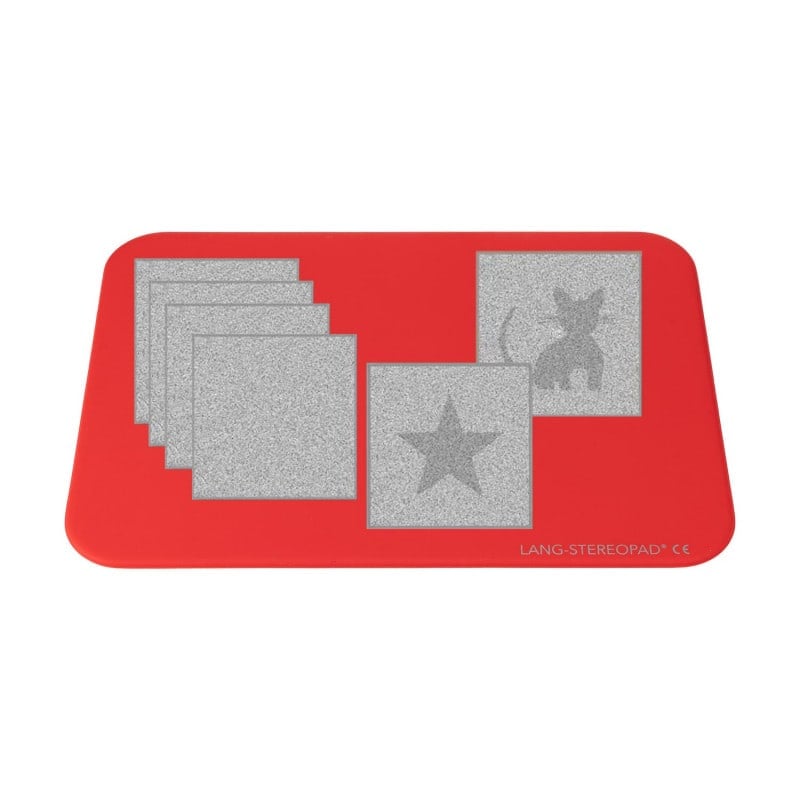

The Lang Stereopad® from Lang-Stereotest AG is an innovative test system for the assessment of global near stereopsis. The system contains six magnetic test cards, each with a 3D random dot stereo object, and operates according to the same principle as the proven LANG-STEREOTEST® I and II as well as the LANG-STEREOTEST® I-R.

The magnetic test cards can be arranged and displayed individually or in groups on the red test panel. The objects on the test cards are perfectly camouflaged - both when viewed with one eye and with the lens grid running horizontally. Due to its special mode of operation, the test is ideally suited for simple screening, determining the stereo threshold or screening with the Preferential Looking method. In addition, the test can be performed without test glasses and guessing the objects is not possible.

- With 6 magnetic test cards

- Cards with one 3D random dot stereo object each

- Can be used individually or in groups

- Double-sided test panel

- Lenticular test cards (plastic framed, magnetic)

- Double-sided test plate, red

- 6 magnetic lenticular test cards (objects: STAR 1000", CAR 600", Cat 400", MOON 200", SUN 100", STAR 50"